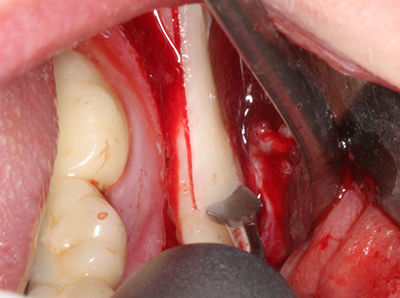

Bei der Knochenblockentnahme zeigen sich weitere Vorteile für die Piezochirurgie: Neben der bereits beschriebenen hohen Präzision bei der Osteotomie stellt sich gerade die Verwendung der dünnen Sägespitzen als besonders materialschonend heraus. Bei der Verwendung insbesondere von Lindemannfräsen sind mit deutlich höheren Entnahmeverlusten durch die dickere Instrumentenspitze zu rechnen (Lakshmiganthan, Gokulanathan et al. 2012). Die insbesondere bei retromolar entnommenen Blocktransplantaten notwendige basale Abtrennung wird durch speziell hierfür vorgesehene rechtwinklige Sägen erleichtert, so dass die Piezochirurgie als präzises, übersichtliches und sicheres Verfahren zur retromolaren Knochenblockgewinnung angesehen wird (Happe 2007) (Abb. 1-12).